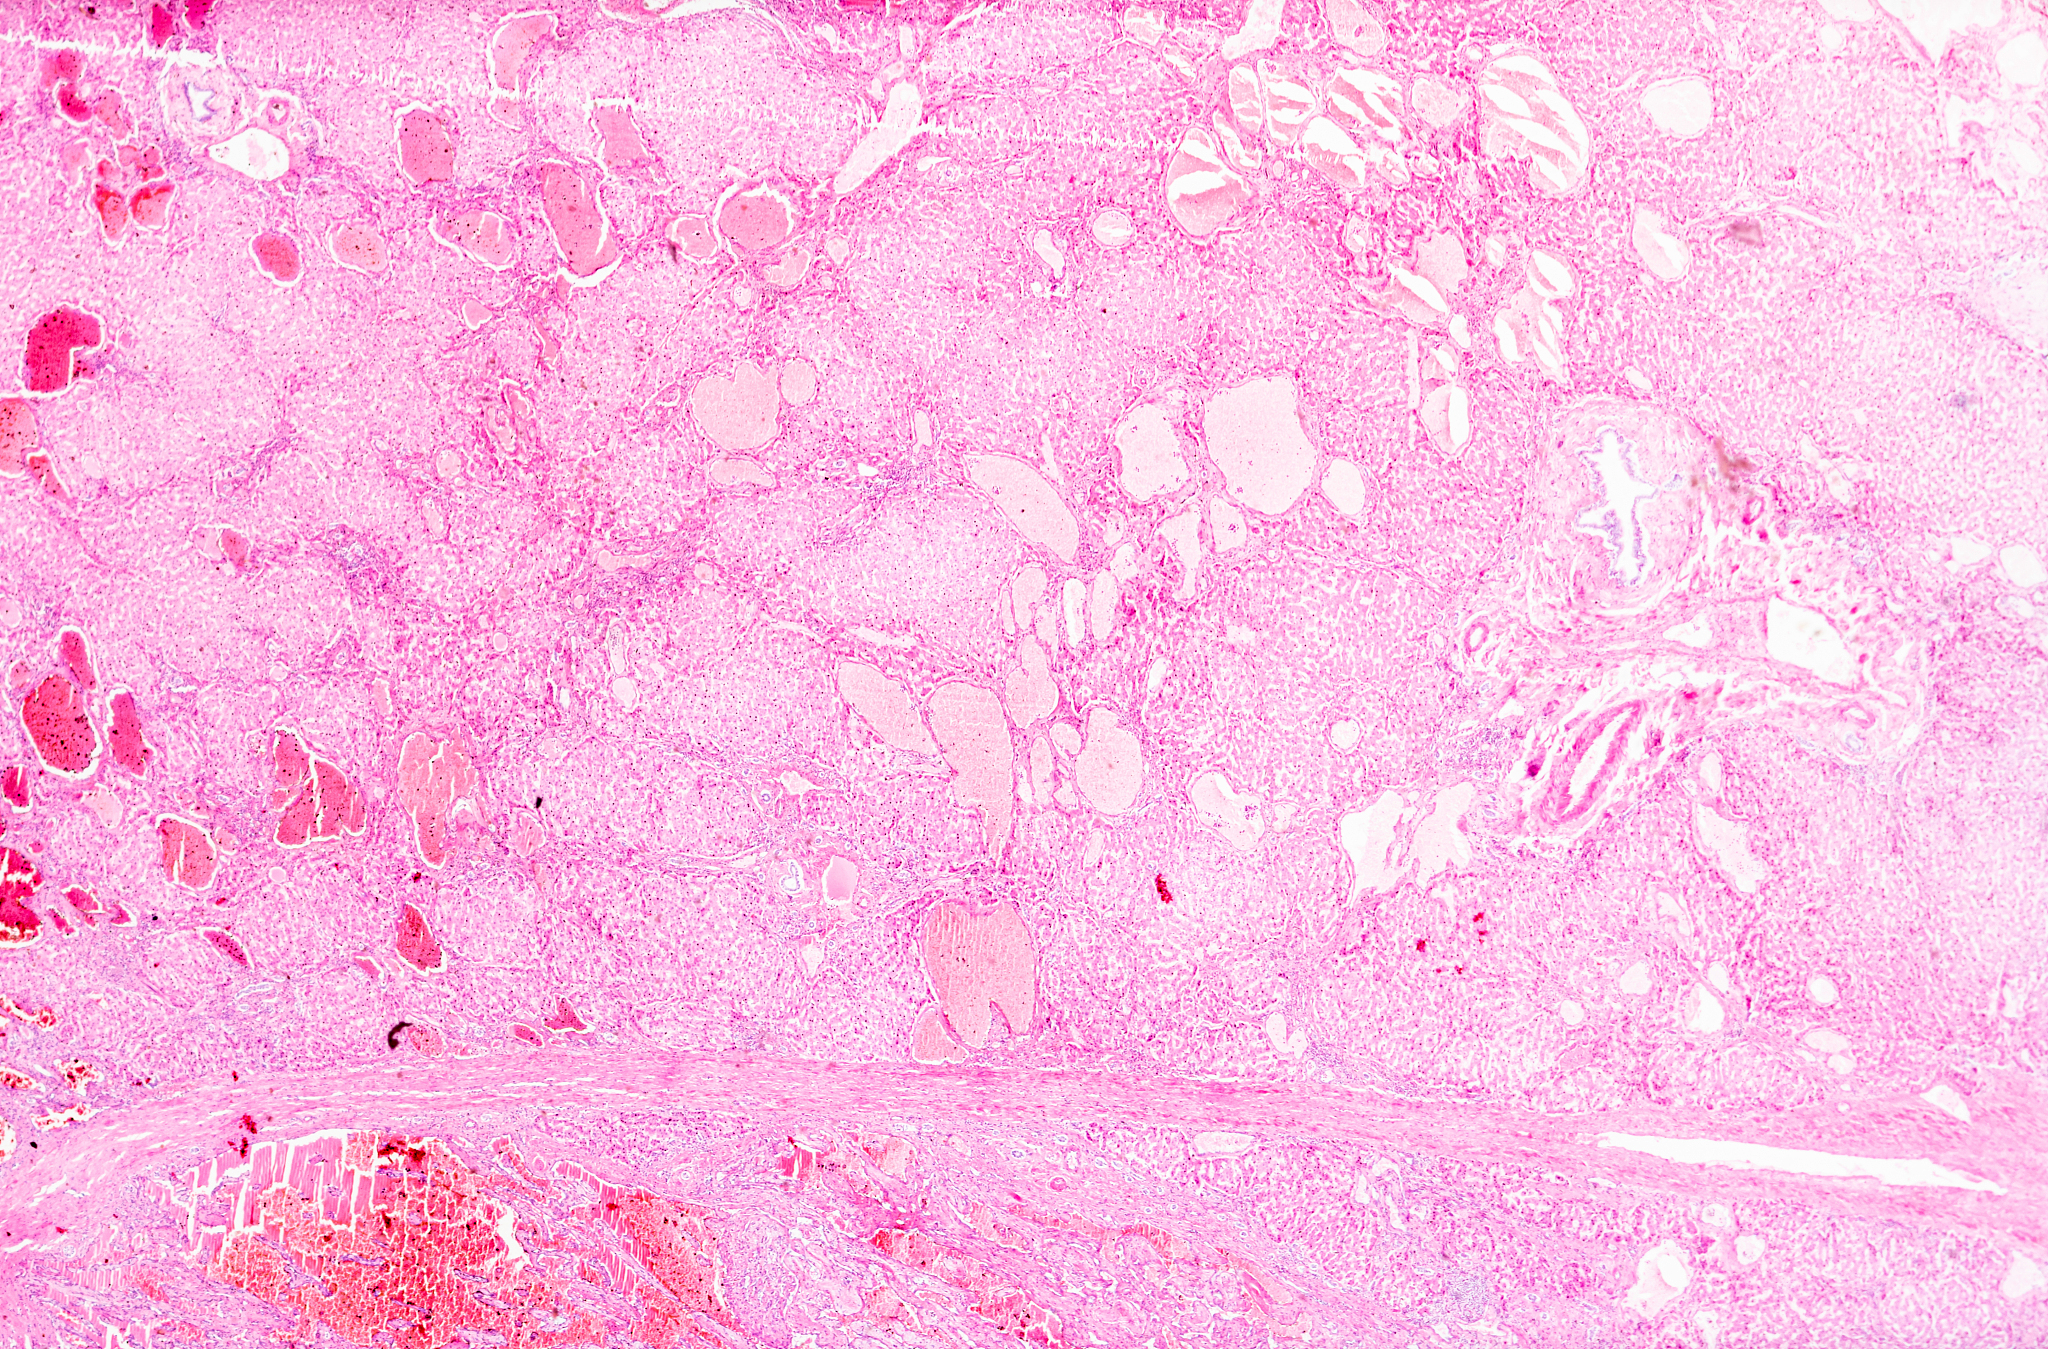

肝血管瘤是肝脏最常见的良性肿瘤,由血管内皮细胞异常增生形成。绝大多数肝血管瘤生长缓慢,不会恶变,通常是在体检时偶然发现。根据大小可分为小型、大型和巨大血管瘤。